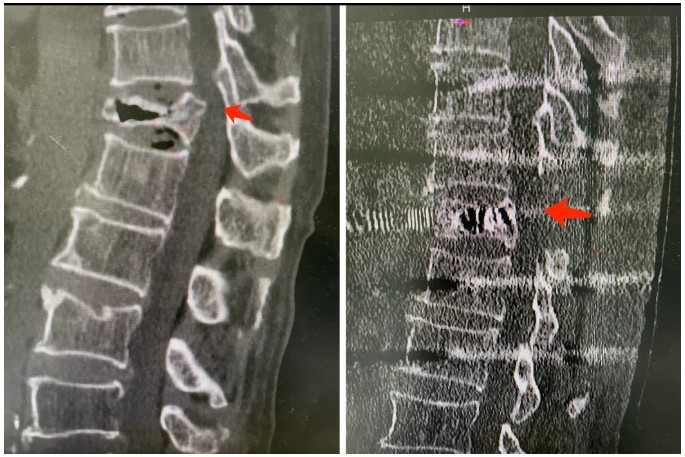

手术通过背部入路完成。杜盛阳带领团队首先解除对脊髓神经的压迫,随后在塌陷的椎体内部植入一个特制的cage支撑装置,恢复椎体高度并重建前柱稳定,同时通过螺钉固定系统稳定脊柱整体结构。

杜盛阳形象地解释:“可以把这个装置理解为一个‘支撑架’,既能在塌陷的椎体内部把脊柱重新撑起来,恢复解剖高度,又能通过固定装置把脊柱稳定住,实现生物力学重建,彻底解除神经压迫。”

术后复查ct可见术前压迫解除,骨折处得到支撑